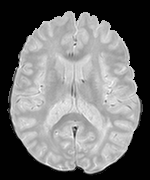

We observed that memberships predicted with an FC layer result in more false positives compared to a fully convolutional network. An example is shown in Fig. 2, where lesion memberships are generated from MPRAGE and FLAIR using the proposed model of convolutional pathways and a comparable model where the last convolutional pathway after concatenation (see Fig. 1) is replaced with a FC layer predicting voxel-wise memberships. The membership image generated with an FC layer, although being close to inside the lesions, has high values () in the left and right frontal cortex where the FLAIR image shows some artifacts. However, the membership obtained with the proposed method shows relatively low values near the frontal cortex.

With FC layer, voxel-wise predictions are performed for each voxel on a new image. Therefore the prediction time for the whole image comprising millions of voxels can take some time even on a GPU, as mentioned in Wachinger et al. (2017). In contrast, with fully convolutional prediction, lesion membership estimation of a mm3 MR volume of size takes only a couple of seconds. Note that although patches are used for training, the final trained model contains only convolution filters and does not depend in any way on the input patch size. Therefore during testing, the lesion membership of a whole 2D slice, irrespective of the slice size, is predicted at a time by applying convolutions on the whole slice. Without an FC layer, the images need not be decomposed into sub-regions, e.g., Kamnitsas et al. (2017). Consequently, there is no need to employ membership smoothing between sub-regions. In addition, since the training memberships, generated by Gaussian blurring of hard segmentations, are smooth, the resultant predicted memberships are also smooth (Fig. 2 last column).